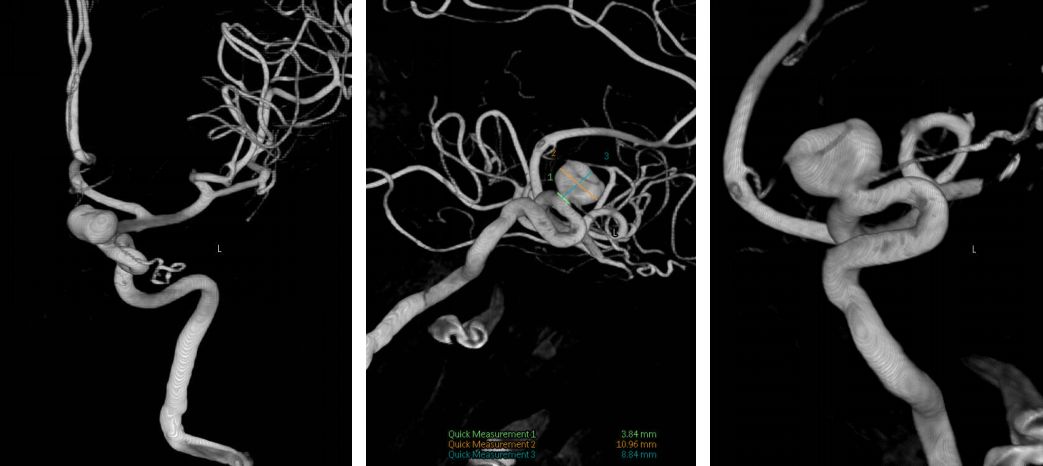

1. 术前CTA: